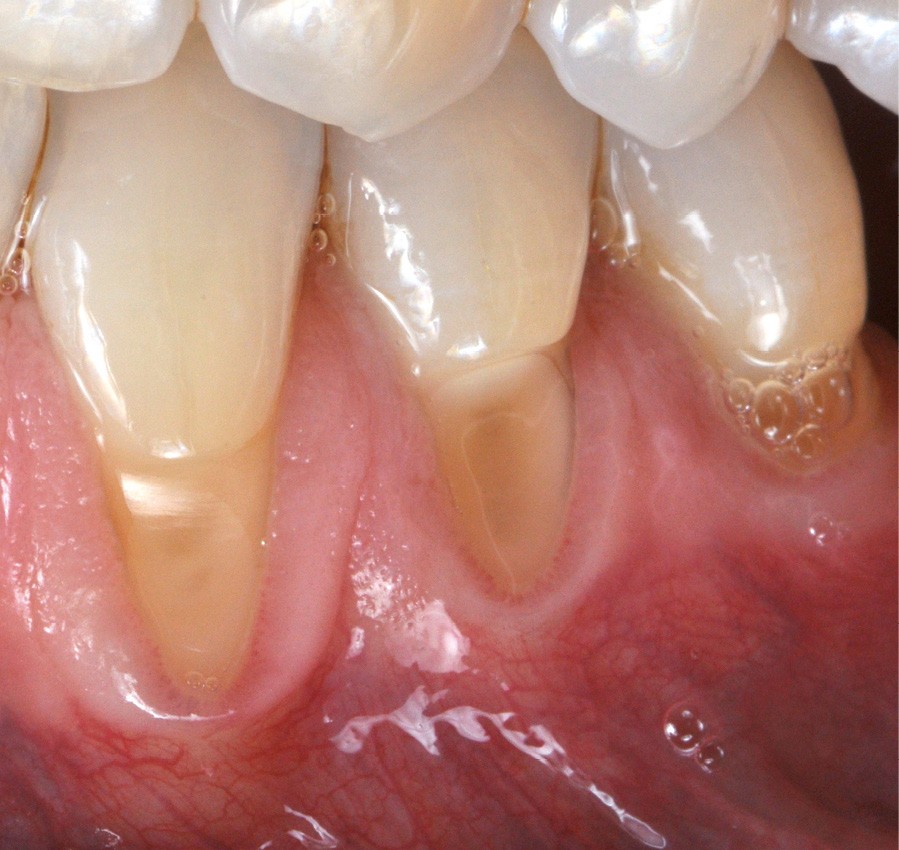

Zuchelli et coll. [1] définissent quatre causes à l’origine des récessions gingivales à la suite d’une déhiscence osseuse : les causes traumatiques (fig. 1) par le brossage, le surcontour prothétique, les piercings ; les causes bactériennes (fig. 2) liées à une inflammation marginale ; les causes virales par le virus de l’herpès simple ; et les origines mixtes, à savoir traumatiques et bactériennes (fig. 3). Le diagnostic de récession liée à la plaque dentaire dépend de la présence de dépôts tartriques et/ou d’inflammation des tissus environnant les zones exposées. En présence d’une origine mixte, la récession est d’abord initiée par un brossage traumatisant, rendant la surface radiculaire hypersensible ou irrégulière, ayant une répercussion négative sur le brossage et l’accessibilité à l’hygiène.